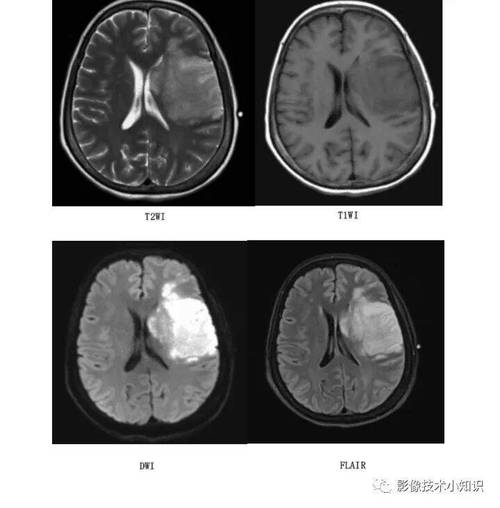

(图片来源网络,侵删)- 核磁: 可以在发病后30分钟到1小时内就发现脑梗死的迹象,它对早期细胞内的水分变化非常敏感,一旦脑细胞开始缺血坏死,DWI序列上就会显示出高信号(亮点)。

- 核磁: 能够更好地鉴别脑梗和脑出血,通过其他序列(如FLAIR、ADC)可以帮助判断梗死的时期,是急性期还是亚急性期。